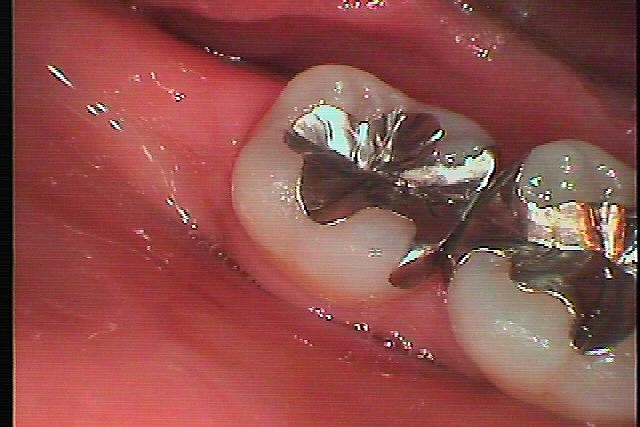

ブログ一覧|広島市安佐南区の歯科医院 ブログ一覧 トップ ブログ一覧 お知らせ スタッフブログ ブログ一覧 お知らせ 2019/10/11 保険の銀歯のブリッジの下が虫歯になり、白いジルコニアブリッジにやり変えていきます お知らせ 2019/10/11 左下の7番、銀歯を外し白いセラミックにやり変えていきます お知らせ 2019/10/10 右下6,7番の銀歯をやり変えたい きれいな白いセラミックにやり変えたい お知らせ 2019/10/10 左上5番の銀歯を外して虫歯治療をしていきます お知らせ 2019/10/09 左下の銀歯を白くしたい 金属を外してきれいにしたい 歯のエステみたいです お知らせ 2019/10/09 右上の奥歯の根の治療からのセラミック治療へ 場t氏は最終手段にて 歯の保存を考える お知らせ 2019/10/08 右上5番インプラント埋入をしていきます 歯を抜き、待ってから埋入しています お知らせ 2019/10/08 右下5番のインプラント埋入 埋入後3か月の後には最終補綴が仕上がります << 1 2 3 4 5 … 379 380 381 382 383 … 870 871 872 873 874 >> Web診療予約 初めての方へ 選ばれ続ける理由 院内設備について 歯が痛いしみる一般歯科 歯がぐらぐらする歯周病 健康な歯を保ちたい予防歯科 子供の虫歯予防をしたい小児歯科 銀歯をセラミックに審美歯科 白い歯を目指しませんか?ホワイトニング 矯正専門医がいるので安心矯正歯科 抜けた歯を補いたいインプラント・入れ歯 医院案内 スタッフ紹介 メリィハウス歯科クリニックオフィシャルホームページ ラベンダー歯科クリニックオフィシャルホームページ お知らせ・ブログ ホーム 診療科目 一般歯科 歯周病治療 予防治療 小児歯科 審美治療 ホワイトニング 矯正歯科 入れ歯・インプラント マウスピース矯正 初めての方へ 院長・スタッフ 設備紹介 医院案内・アクセス メニューを閉じる